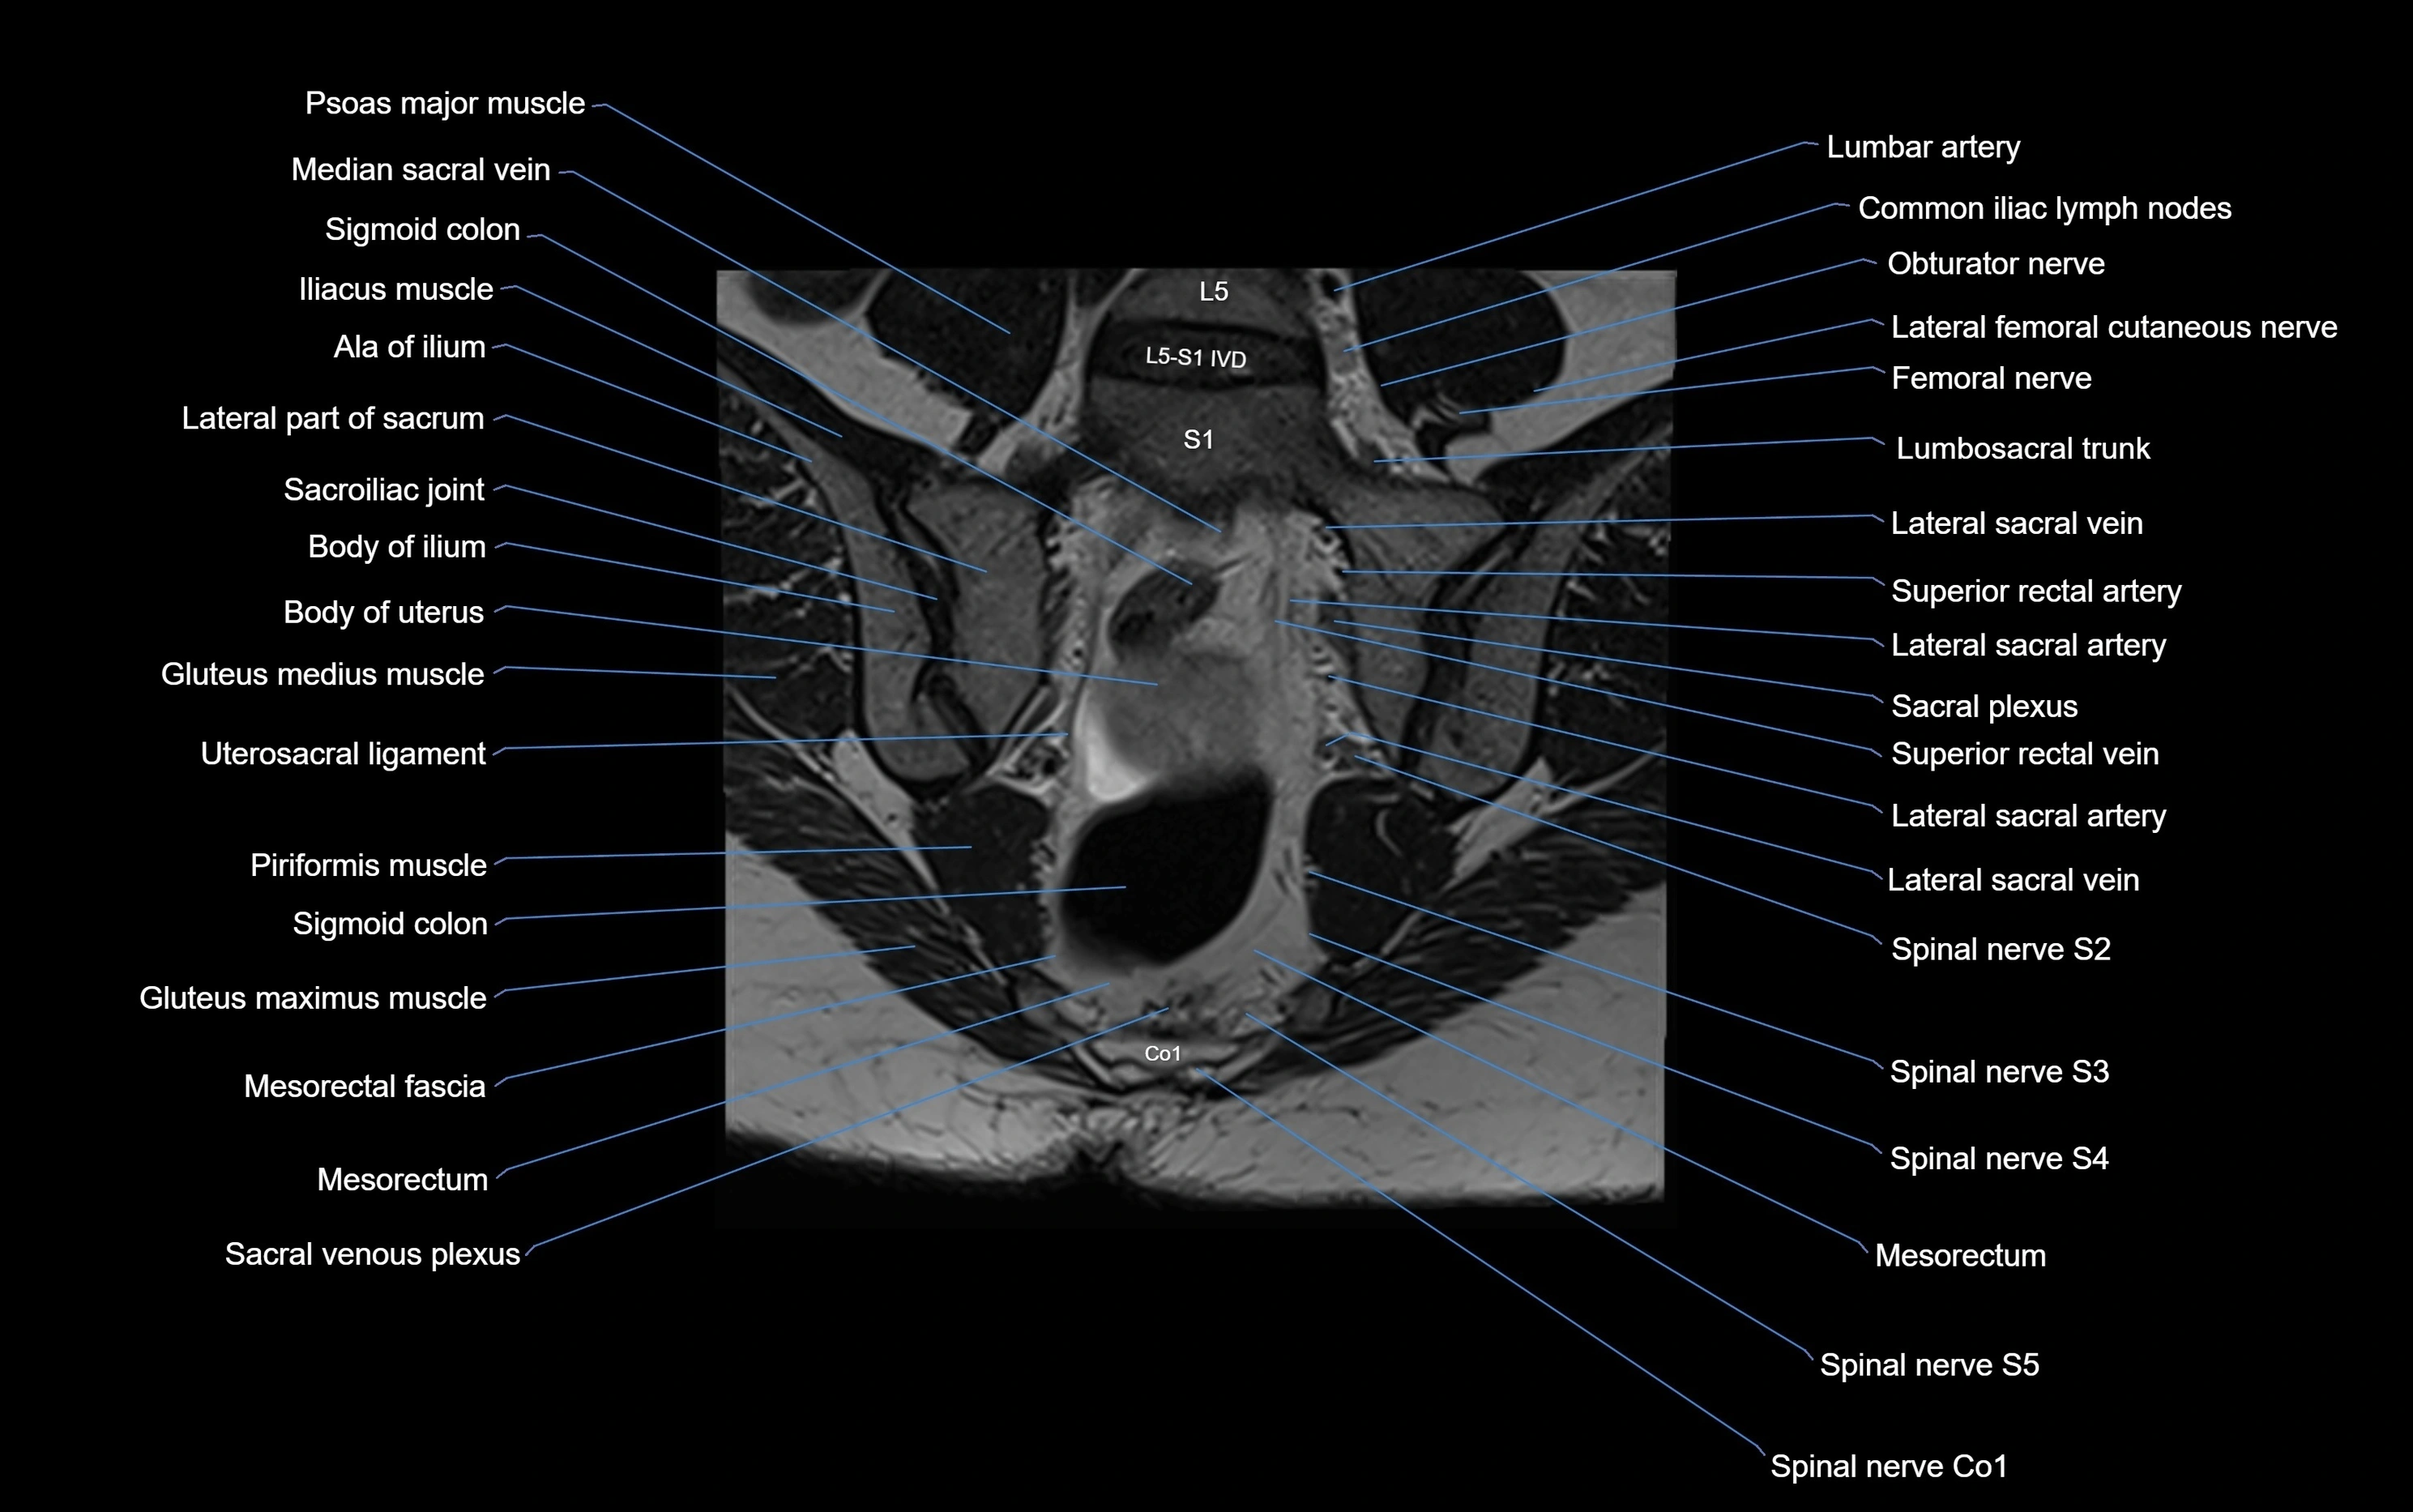

MRI image

image